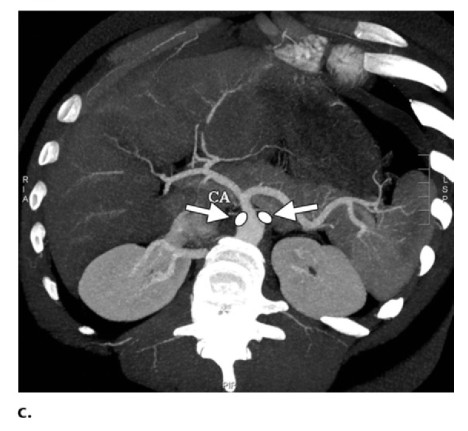

Alcoolisation rétrocrurale du plexus coeliaque

Alcoolisation rétrocrurale du plexus coeliaque à visée antalgique

Technique :

Geste réalisé sous anesthésie locale, sous contrôle scanner.

Repérage scanner retrouvant [XXX] et identifiant les espaces graisseux rétrocruraux entre T12 et L2, cibles du geste.

Sous contrôle scanner, mise en place dans l'espace graisseux rétrocrural cible de chaque côté d'une aiguille spinale noire 22G.

Injection de produit de contraste (1 ml de chaque côté). Confirmation par scanner de la bonne position des aiguilles.

Scanner de contrôle montrant une bonne diffusion craniocaudale du produit de contraste dans l'espace rétrocrural de chaque côté.

Alcoolisation bilatérale rétrocrurale du plexus coeliaque.